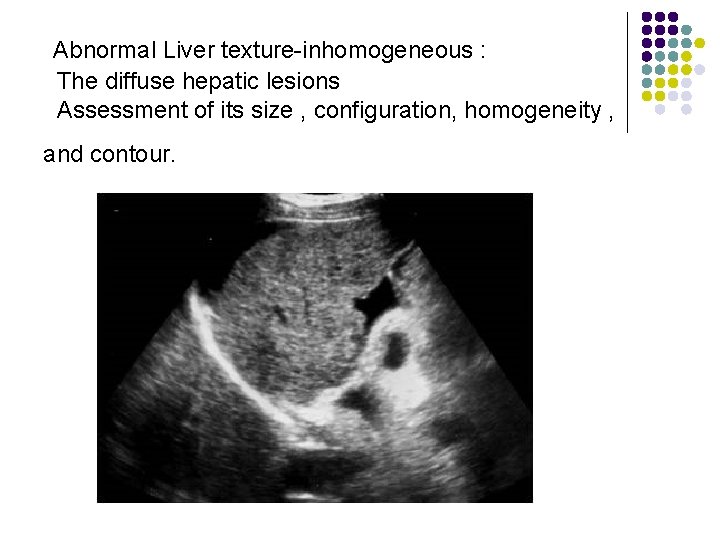

Abnormal Liver texture-inhomogeneous : The diffuse hepatic lesions Assessment of its size , configuration, homogeneity , and contour.

Assessment of its size , configuration, homogeneity , and contour